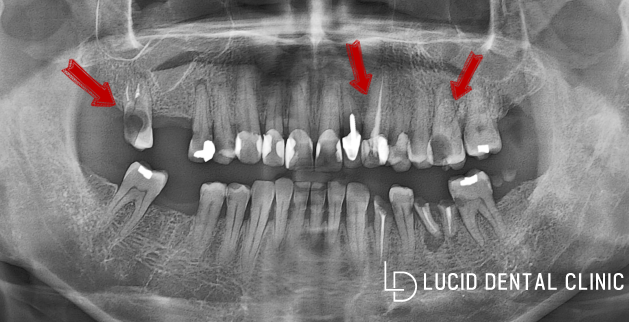

전체 구강 현황을 살펴볼 수 있는

파노라마 엑스레이 사진인데요.

한눈에 봐도 상태가 안 좋아 보이죠?

현재 충치 감염이 심하게 나타나

치관(머리 부분)까지 소실되었고,

아예 발치하여 비어있는 부분도

관찰되고 있어 상황이 심각했습니다.

표시된 부분들은 충치가 신경을

넘거나, 근접하게 진행되었는데요.

신경치료를 통해 보존할 수 있으나,

우식증이 나타난 곳을 삭제하는 도중

신경과 근접하게 되면 나중에 보철을

씌울 공간이 없어 체결이 어렵습니다.

아무래도 신경치료와 임플란트 수술

두 가지를 병행하여 개선해야겠습니다.